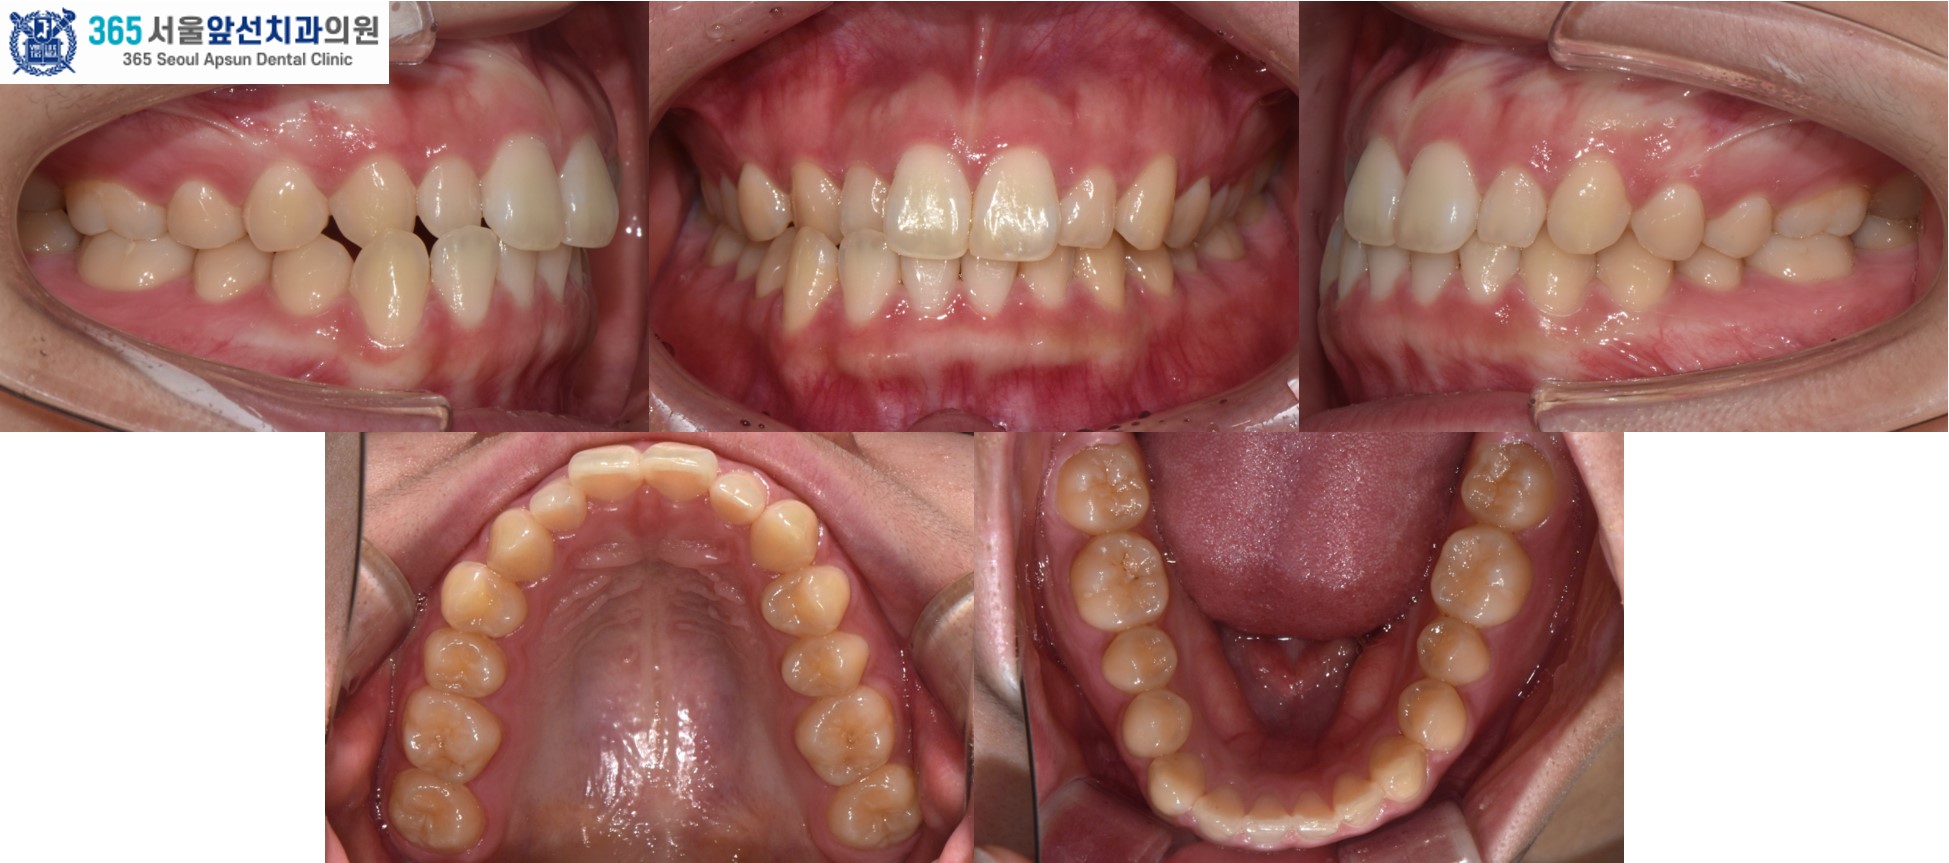

촬영일시 : 2025.11.12. 치료 후의 모습입니다. 2024년 11월 16일 치료를 개시하여 2025년 11월 12일에 교정치료를 종료하였으며 총 12개월의 치료기간이 소요되었습니다. 치열이 가지런하게 배열되었고 목표하였던 반대교합의 해소, 정중선 불일치 개선이 완료되었습니다. 왜소치 수복 없이 구치부 1급 관계와 견치 유도 및 전치 유도가 가능한 교합이 잘 만들어졌습니다. 더불어 입술의 비틀어짐도 자연스럽게 해소되셨습니다. ![]() 촬영일시 : 2024.10.23. / 2025.11.12. 앞니의 반대교합이 있으셨던 환자분의 12개월 간의 치료 증례를 소개해드렸습니다. 환자분께서 정기적인 내원에 적극 협조해주셔서 치료기간이 단축되었던 것 같습니다.^^ 반대교합, 정중선 불일치, 비뚤한 치열이 고민이신 환자분들께서는 내원하셔서 교정 진단 받아보시길 바랍니다. 감사합니다.